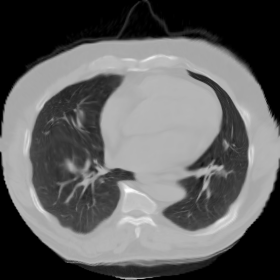

Figure 9. The lung CT example.

7.3. Real CT images

We now consider applying the proposed image registration method on real lung CT images retrieved from the National Lung Screening Trial (NLST) dataset [1]. Fig. 9(a) and Fig. 9(b) show two slices of lung CT images that we use as the source and the target (see Fig. 9(c) for the absolute intensity difference). We remark that the CT images are originally with different intensity, and so we apply an intensity histogram matching before running the registration experiment. Fig. 9(d) shows the registration result obtained by our proposed method. It can be observed that our method successfully produces a large deformation on the right lung of the source image to match that of the target image (see also Fig. 9(e) for the final absolute intensity difference). On the contrary, DDemons [47] (Fig. 9(f)), LDDMM [5] (Fig. 9(g)), Elastix [29] (Fig. 9(h)) and DROP [18] (Fig. 9(i)) all fail to produce an accurate and bijective registration result. This shows that our method is more capable of handling large deformation image registration.